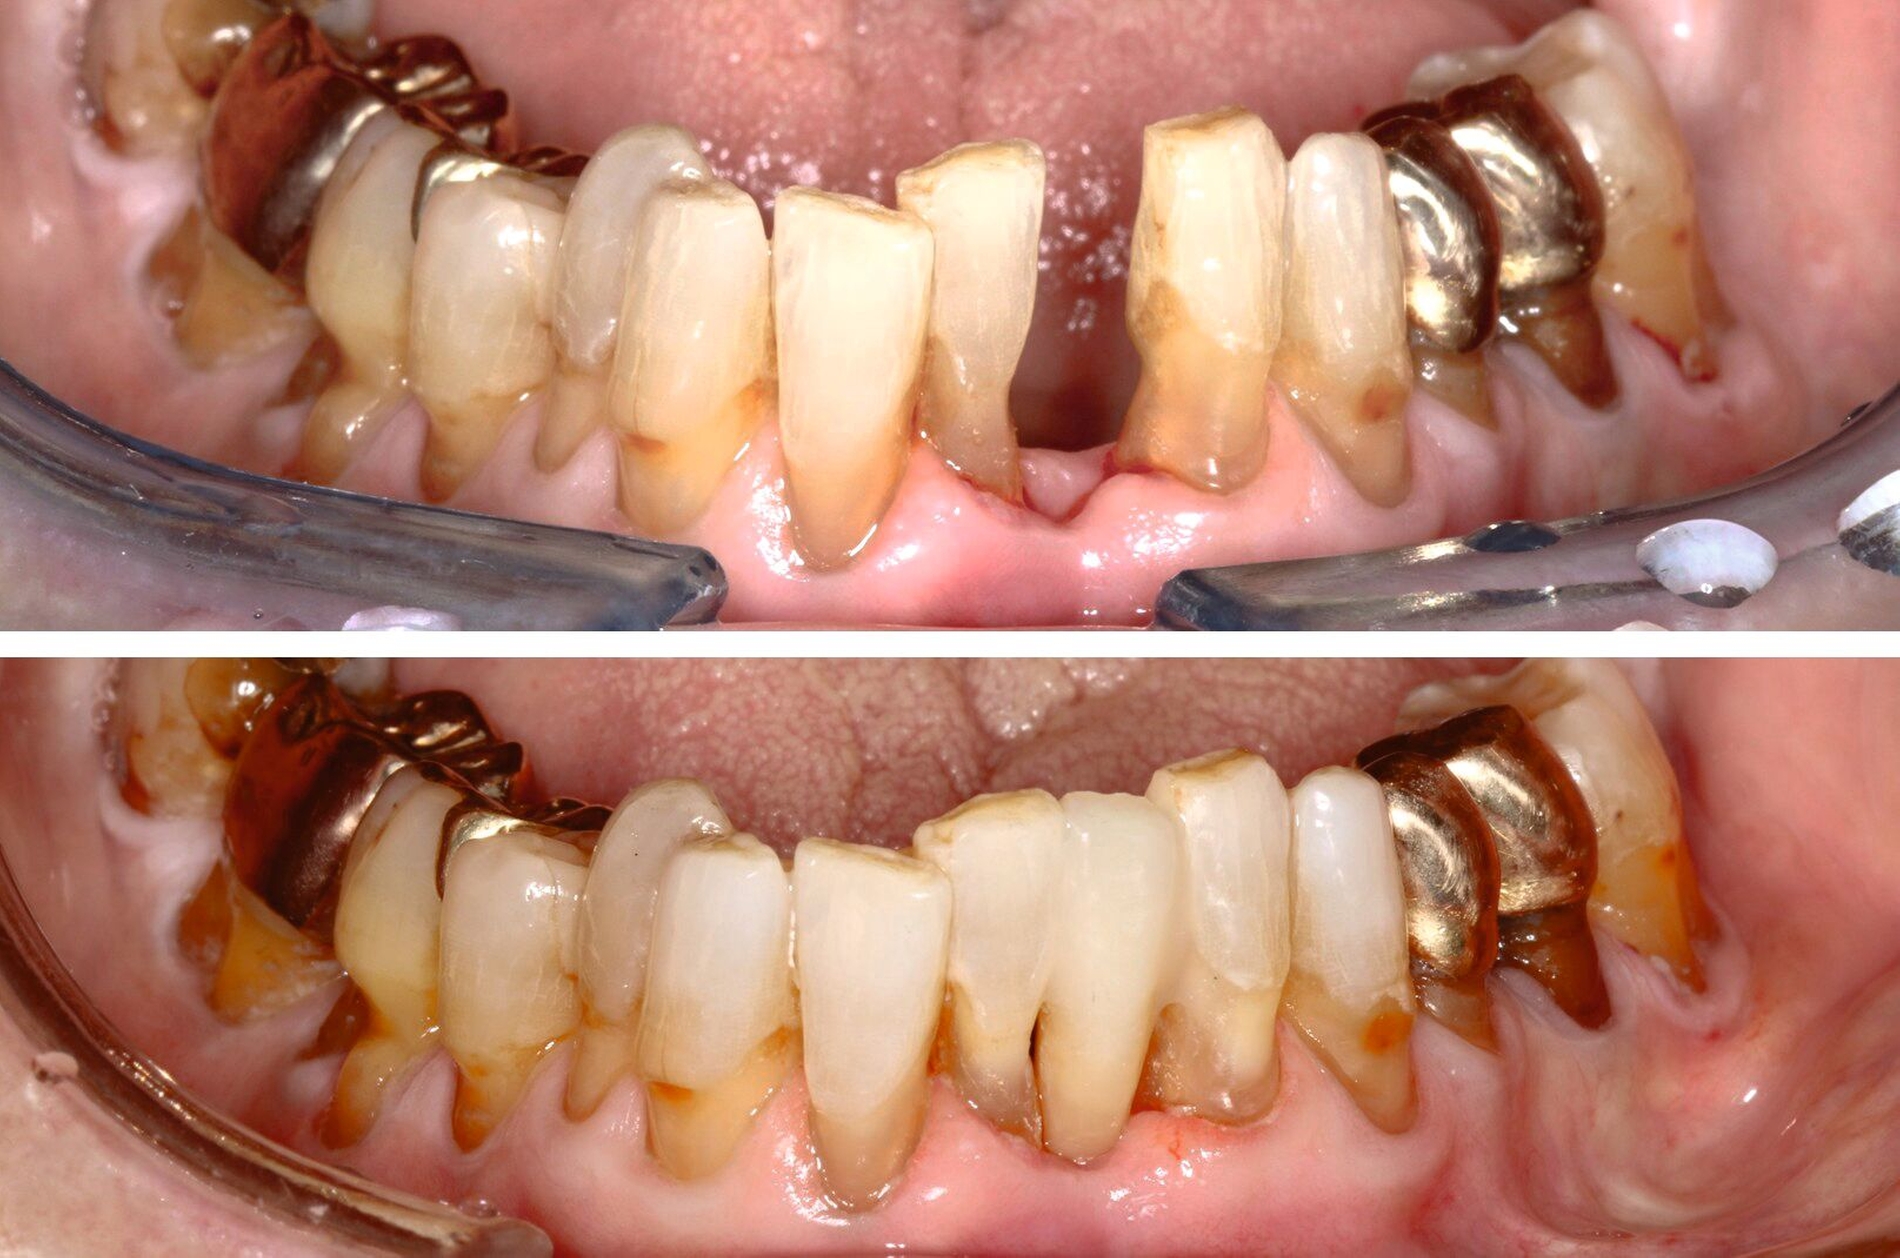

Die hochbetagte Patientin war bereits viele Jahre in der Poliklinik für Zahnerhaltung des Universitätsklinikums Tübingen zahnmedizinisch betreut worden, allerdings aus Sorge vor einer Corona-Infektion von Ende 2019 bis August 2023 knapp vier Jahre der zahnärztlichen Versorgung ferngeblieben. Grund der Wiedervorstellung war dann ein wenige Tage zuvor stattgefundener Füllungsverlust am Zahn 36. Hier bemerkte die Patientin eine an der Zunge störende scharfkantige Fraktur des Molaren (Abbildungen 2 und 3). Weitere Schmerzen oder Beschwerden gab sie nicht an. Im Rahmen der zahnärztlichen Untersuchung konnten multiple Rezessionen und diverse arretierte Brown-Spot-Läsionen festgestellt werden.

Obwohl die unterstützende Parodontitistherapie (UPT) vier Jahre unterbrochen war, konnte bis auf einen Grad III gelockerten Zahn 31 und eine Grad I–II gelockerte, restliche Unterkieferfrontbezahnung ein gut erhaltenes Gebiss festgestellt werden. Dies ist auch darauf zurückzuführen, dass die Patientin – trotz ihres fortgeschrittenen Alters – die häusliche Mundhygiene stets sehr gründlich betrieb, wie auch aus früheren Akteneinträgen ersichtlich wurde (Abbildung 4).

Allgemeinanamnestisch zeigte die Patientin neben einer diagnostizierten Herzinsuffizienz, einer medikamentös behandelten, stabilisierten Angina pectoris und einer Niereninsuffizienz auch eine fortgeschrittene Wirbelsäulenarthritis, wodurch längeres, nach hinten gelehntes Sitzen auf dem Behandlungsstuhl für die Patientin schmerzhaft war und ihre Adhärenz für längere Sitzungen deutlich reduzierte.